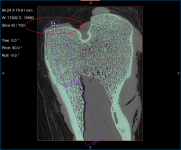

Screen capture of the completed tutorial